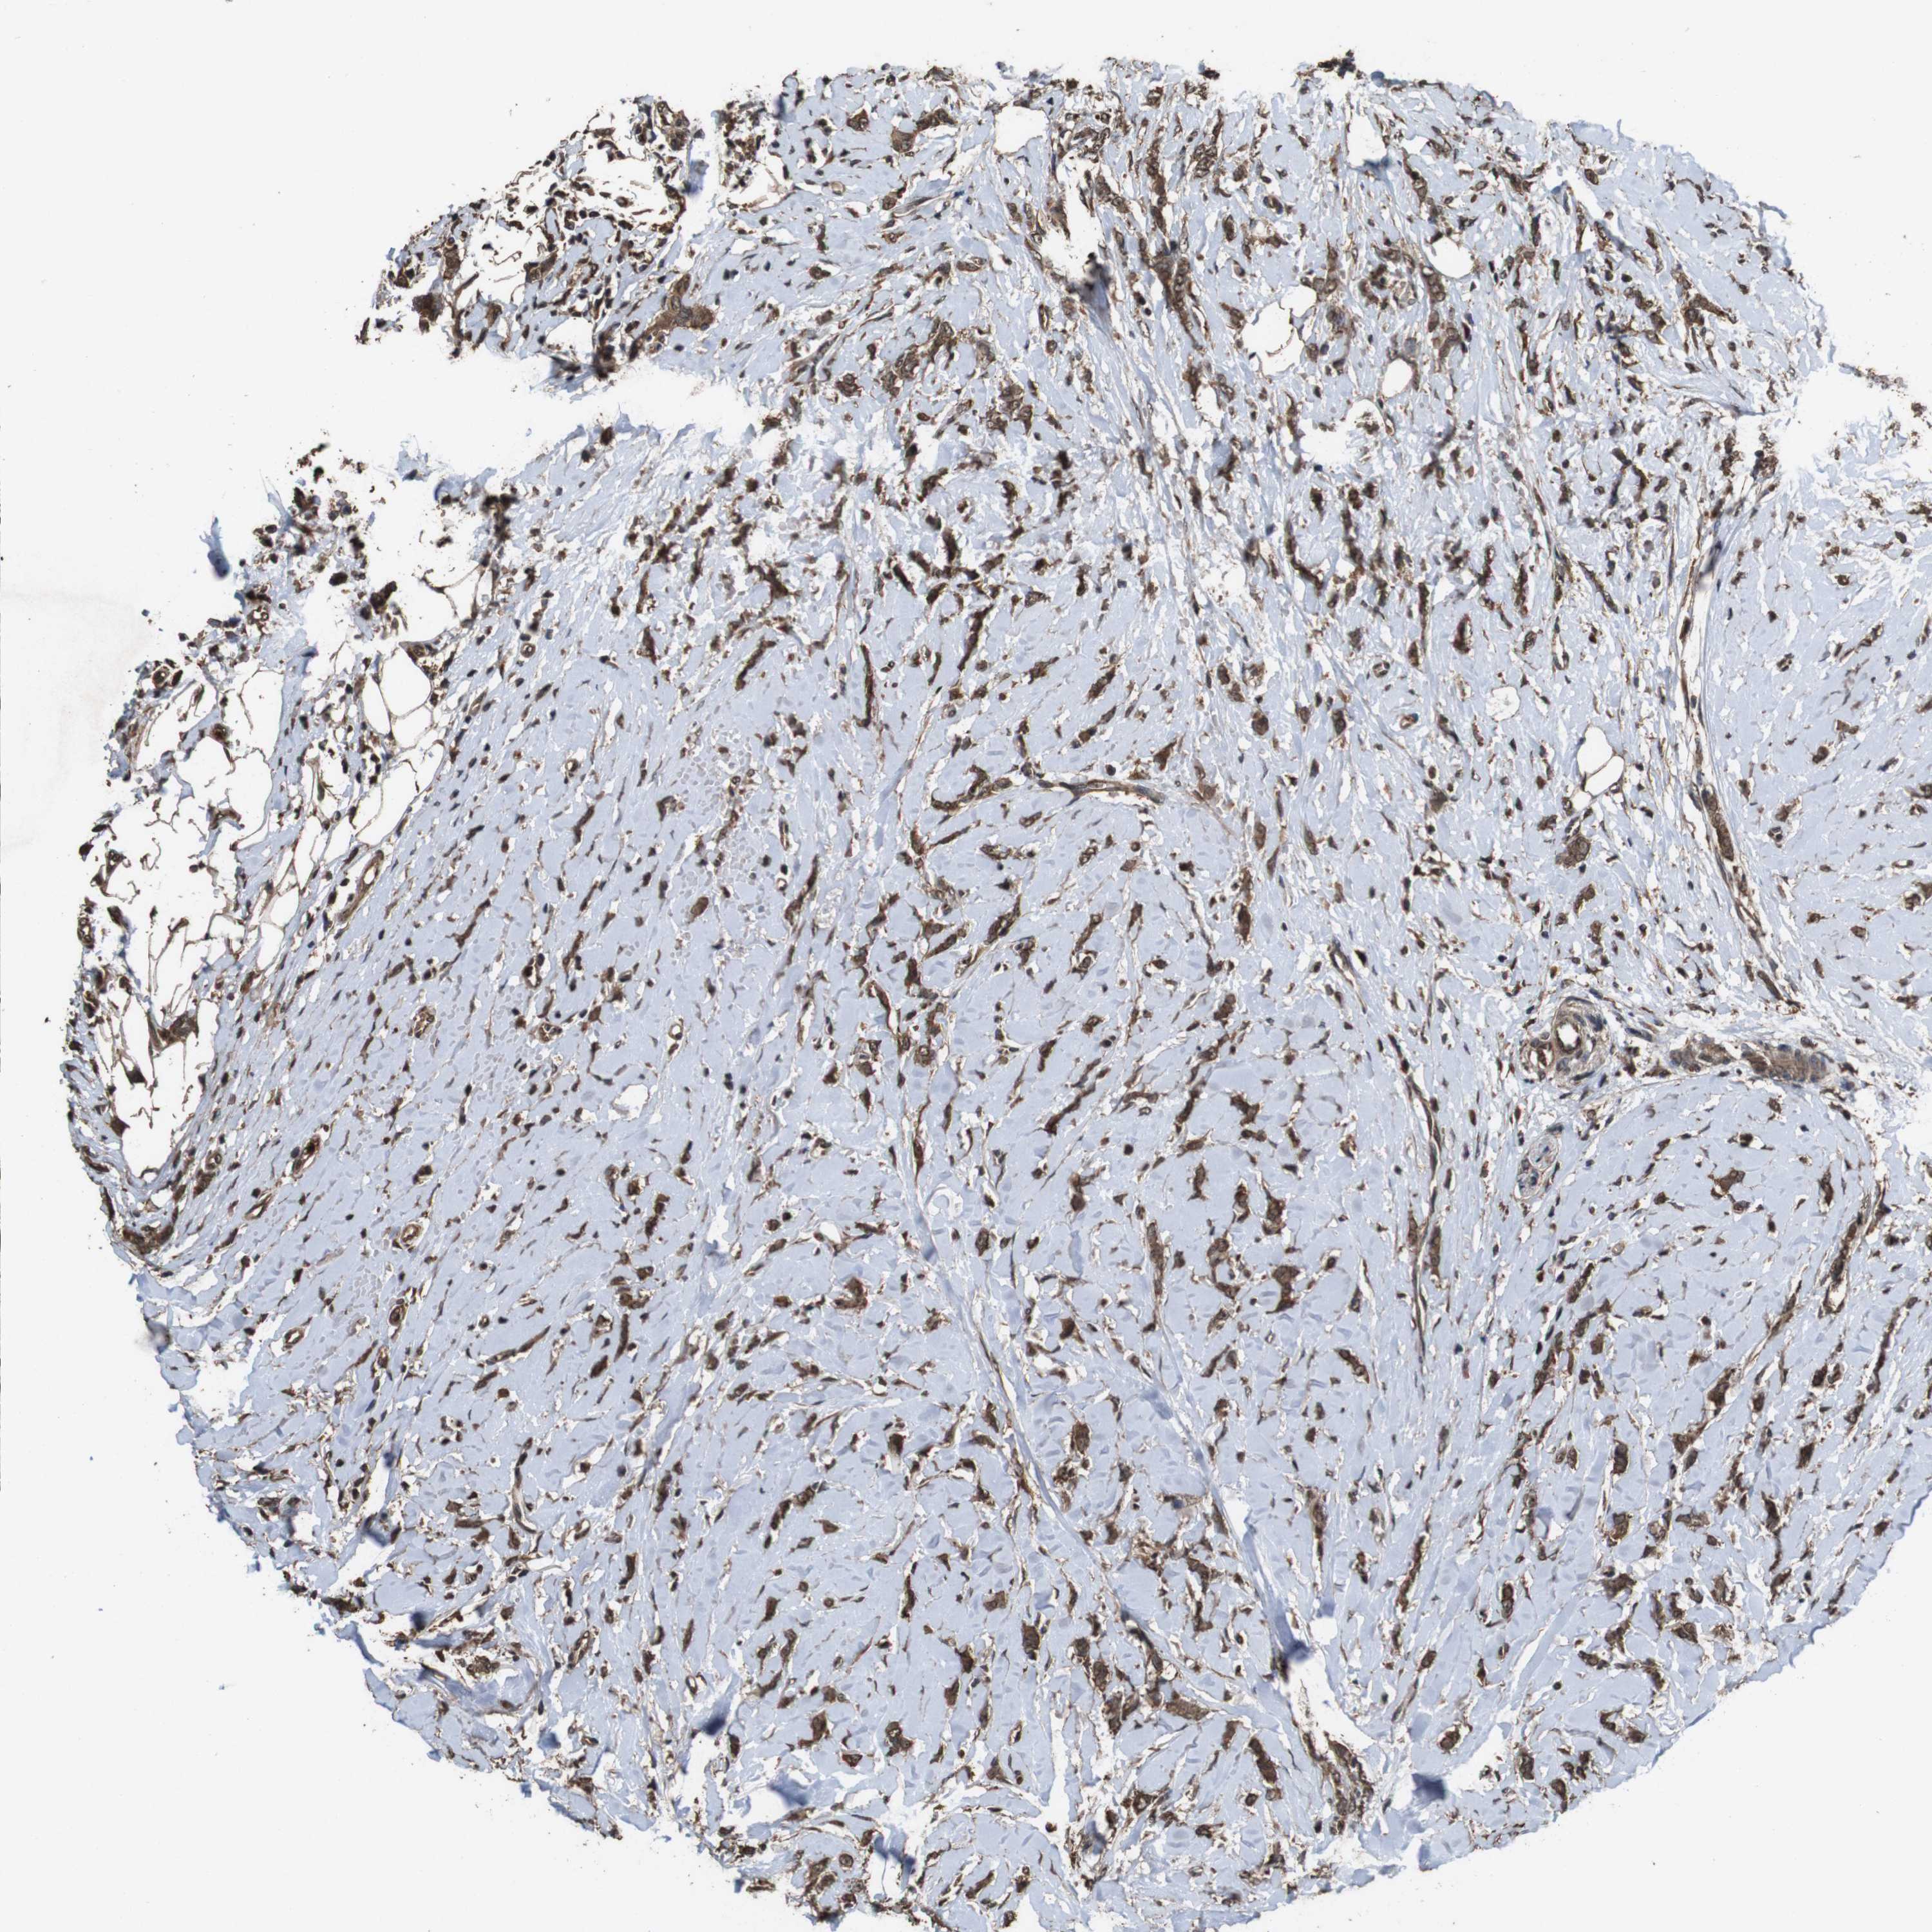

CANCER BREAST CANCER Show tissue menu

BRCA TCGA BRCA VALIDATION PROTEIN EXPRESSION